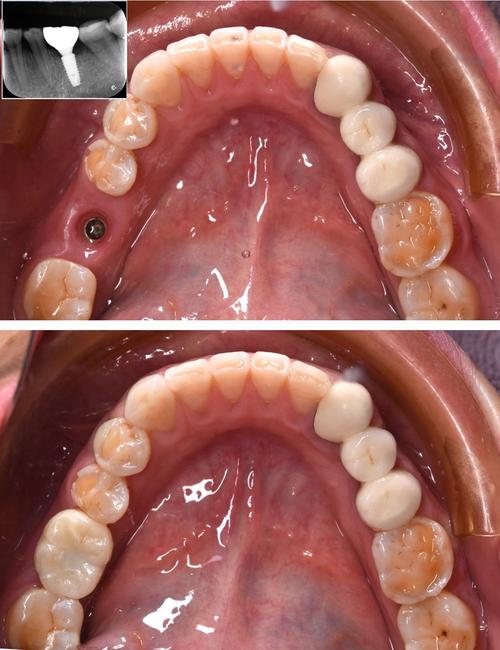

手术过程在严格无菌环境下进行,通常采用局部麻醉,创伤小、疼痛感轻,医生会逐级备洞后将种植体植入牙槽骨,缝合创口后进入愈合期(一般为3-6个月),期间种植体会与骨组织结合(骨整合),待骨整合完成后,安装愈合基台,再取模制作牙冠,最后完成戴牙,整个过程中,九医院注重微创理念,尽量减少对周围组织的损伤,同时利用数字化技术实现精准种植,缩短手术时间,提升患者舒适度。